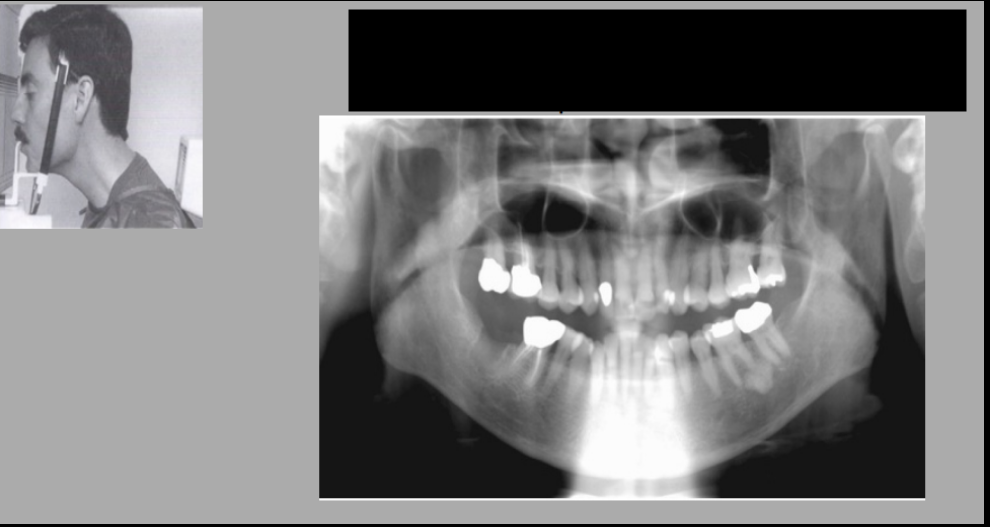

What error is shown in each photo?

Which error is most significant in the way the patient was positioned?

A. Head is turned too much to right

B. Head too far back

C. Head too far forward

D. Head turned to the right too much

What is the most prominent error depicted in positioning of the patient by the radiographer?

A. Chin a bit too far down

B. Chin a bit too high up

D. Head too far back